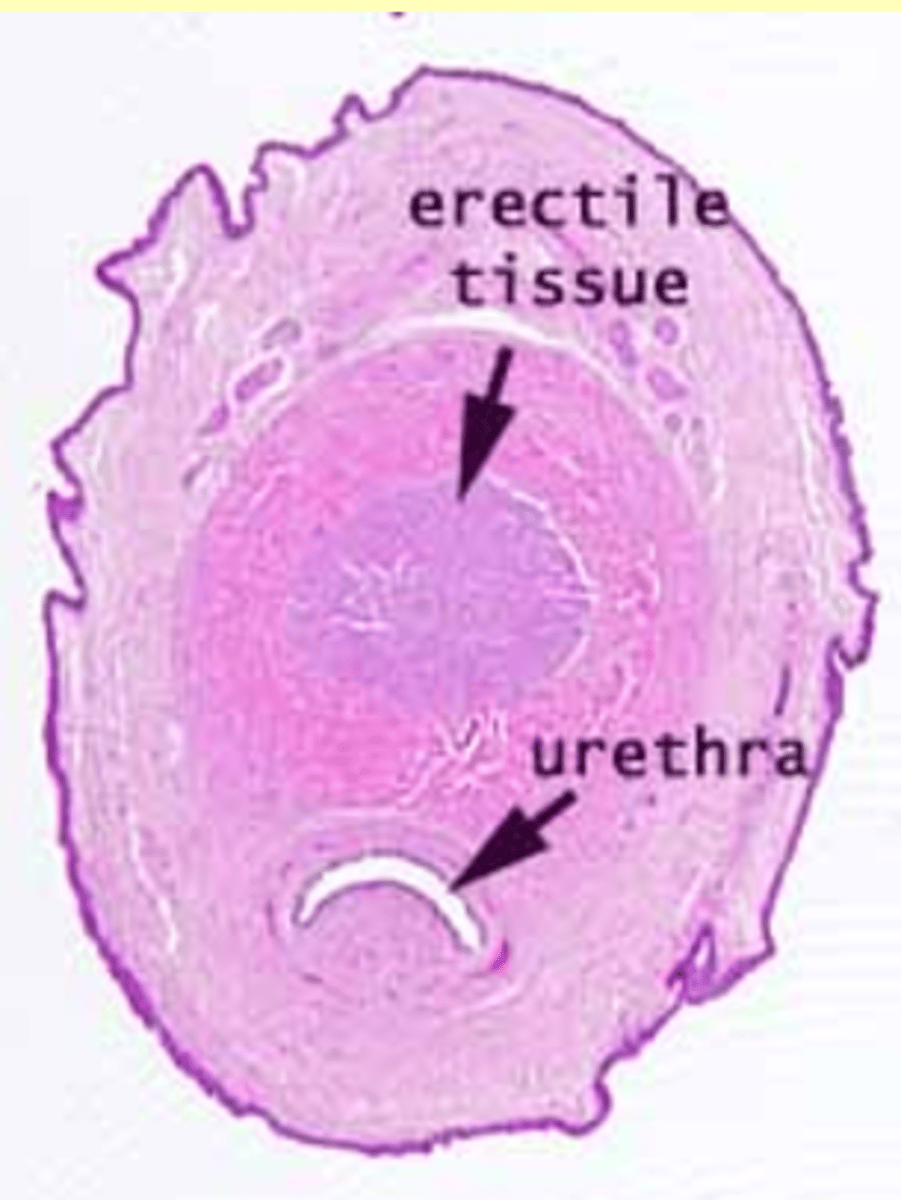

Erectile tissue

Corpus cavernosum

Corpus spongiosum